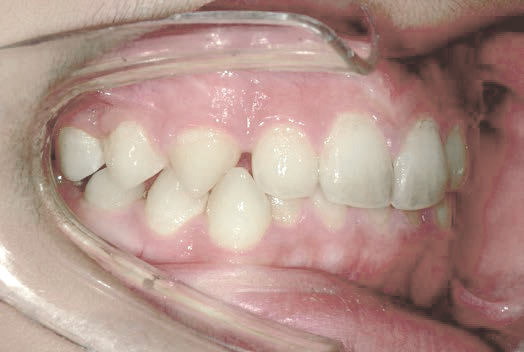

出っ歯

他院で「抜歯して5年かかる」と言われましたが、非抜歯、1年で治りました

Sさん (矯正開始時:12歳)

Before

After

下の奥歯が内側に傾いて、舌の位置が悪く、鼻がつまって口呼吸の状態でした。扁桃腺がよく腫れ、風邪をひきやすく、いびきもあるようでした。

治療を終えて

装置で上あごを拡大し、下の歯の位置を整え、前歯の並びを整えました。お口のトレーニングの効果で鼻詰まりと、いびきも改善。たった1年でこの変化が見られました。もちろん歯は1本も抜いていません。

主訴・治療内容 他院にて「抜歯した上で、ワイヤーを付け、5年かけて治療する」と言われ、他の方法はないのかとネットで調べたところ、当院を知り無料相談に来院されました。

治療期間 1年

費用 462,000円(税込)